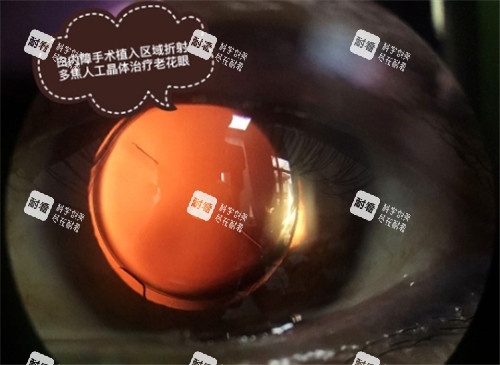

白内障作为常见的致盲性眼病,严峻影响患者的生活质量。

特别是对于经济困难的家庭来说,手术费用往往成为重见光明的拦路虎。